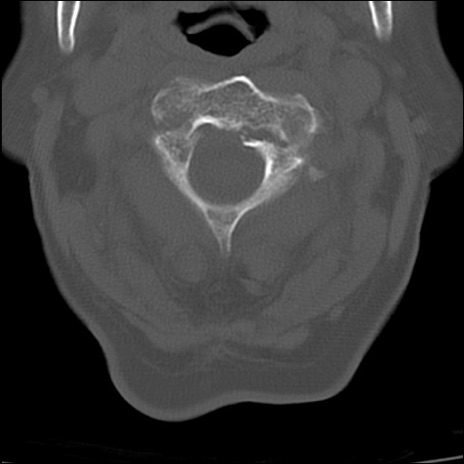

症例48 頚椎CT(横断像)

頚椎CT